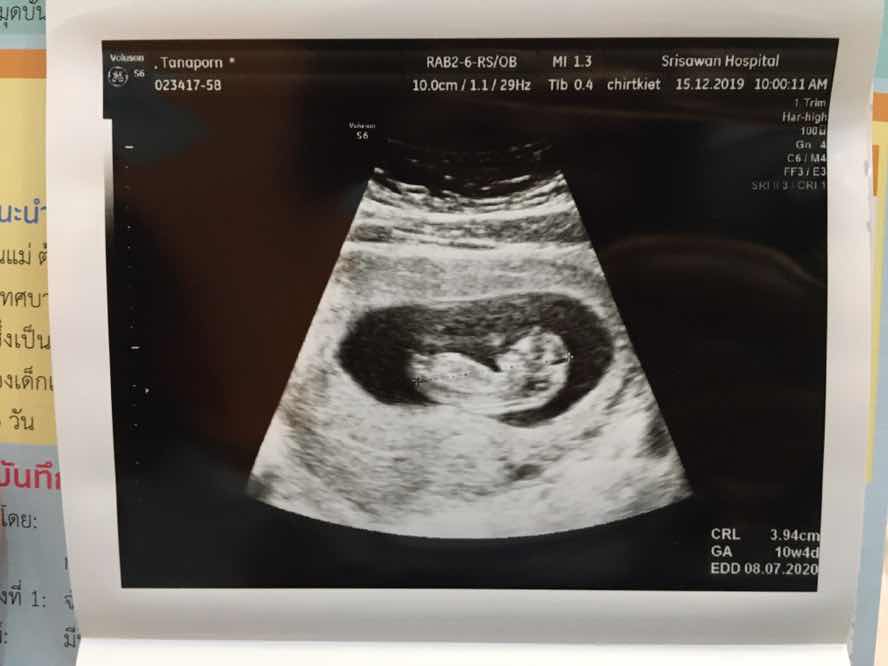

ขอถามเเม่ๆหน่อยค่ะอายุครรภ์ประมาณนี้สามารถซาวได้ยังค่ะจะเห็นร่างกายน้องไหม. ขอบคุนค่ะ

10 w คะ